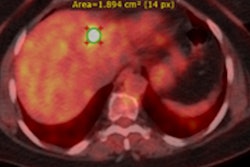

Example of planning CT and CBCT images. A: Treatment planning CT scan. B: kV cone-beam CT scan of the same patient prior to the first treatment fraction. The gross tumor volume is indicated in green. © 2017 van Timmeren JE, Leijenaar RTH, van Elmpt W, et al. (Radiother Oncol, June 2017, Vol. 123:3, pp. 363-369).To explore the potential interchangeability of CT and CBCT radiomic features, Janna van Timmeren from the MAASTRO clinic and colleagues looked at 288 patients from three clinics who had previously been treated for NSCLC. The researchers compared treatment planning CT scans for each patient with the corresponding CBCT image taken prior to the first radiotherapy fraction.